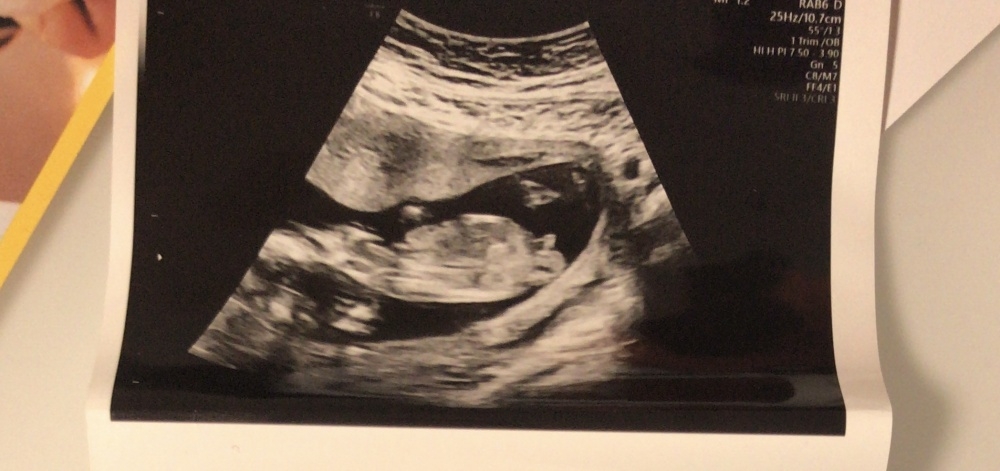

Hallo, ich bin mit Zwillingen in der 23ssw. Beim letzten Ultraschall 19ssw war die Ärztin sich bei einem direkt sicher, dass es ein Junge ist was ich auch so erkannt habe. Beim zweiten war sie sich unsicher meinte aber auch dort einen Zipfel erkannt zu haben. Heute war sie sich bei Baby Nummer 1 auch direkt wieder sicher mit junge. Was man auf Bild Numme 1 erkennt. (Wobei ich nach längeren hinsehen den weißen Strich komisch finde). Bei Baby Nummer 2 war sie wieder etwas unschlüssig und meinte, da ist der Zipfel, hat dann zur Blase geschallt und meinte ne ich guck noch mal und meinte ,

da wieder doch doch das ist der Zipfel. Jetzt finde ich, dass man bei Bild Nummer 2 zwar einen Zipfel sieht der aber im Gegenteil zu Nummer 1 komplett anders aussieht, da ich da auch keine Hoden sehe ? Wie seht ihr das ?🤔